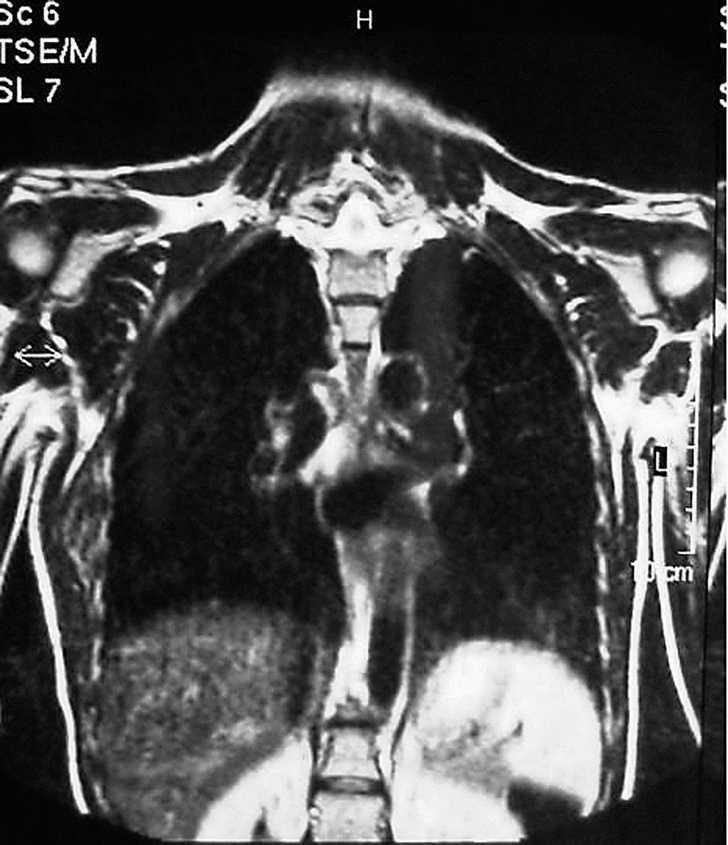

Mujer de 53 años, sin antecedentes de interés, remitida desde el servicio de cirugía general por tumoración en la espalda. La paciente refería dolor periescapular con los movimientos del hombro. En la exploración se observó una lesión abultada en la zona de la punta de la escápula izquierda que aumentaba de tamaño con la elevación y antepulsión del brazo (fig. 3). En la tomografía axial computerizada (TAC) se hallaron dos lesiones bilaterales entre pared torácica y escápulas, de mayor tamaño la izquierda, con apariencia similar al músculo. Lesión muy sugestiva de ED. Se realizó PAAF con resultado de extendido constituido por tejido adiposo. Se solicitó una RMN, que informó de ED bilateral (fig.4). El tratamiento sintomático no logró aliviar el dolor, que comenzó a ser bilateral. Finalmente se realizó una resección marginal de la tumoración sin complicaciones, obteniendo una pieza de aproximadamente 7 x 9 x 4 cm (fig. 5), analizada por anatomía patológica con el resultado de ED.

Figura 4. Elastofibroma dorsi bilateral.